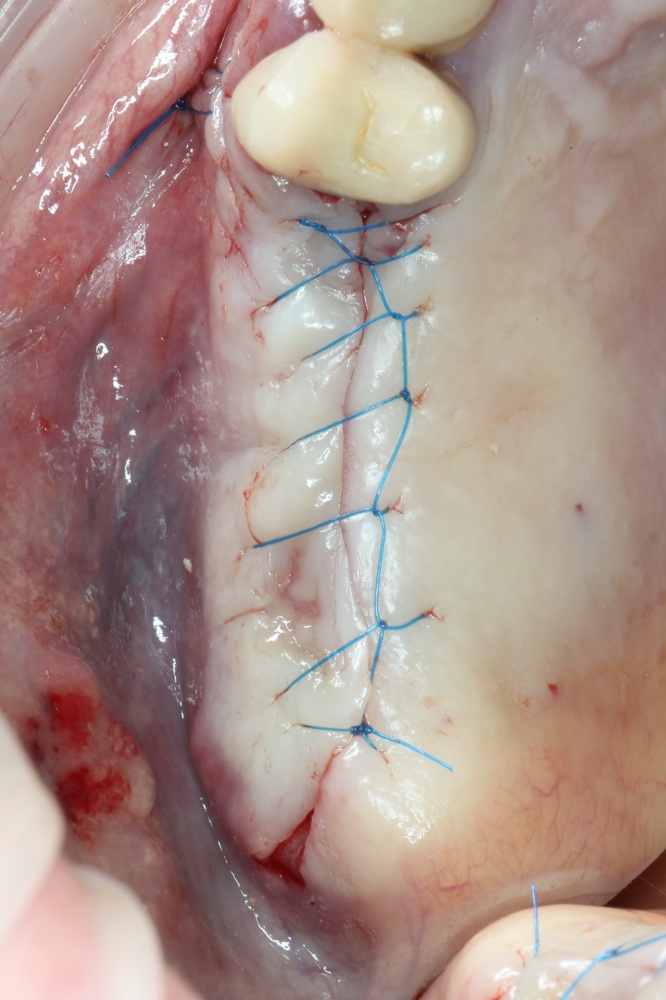

Наложение швов.

Если на этапе разреза и формирования раны всё сделано правильно, то наложение швов не вызывает особых трудностей. Периостотомия или послабляющие разрезы на периосте не требуются (ни практически никогда не требуются). А сами швы получаются аккуратными и герметичными:

Обрати внимание, что все шовные лигатуры находятся в пределах кератинизированной десны. Это позволяет избежать деформации тканей и лишних рубцов. В наиболее уязвимых местах (около зубов) шовные лигатуры лучше продублировать.

Если бы мне пришлось делать это сейчас, то я бы использовал непрерывный «матрацный» шов. Он удобнее, быстрее в наложении и комфортнее для пациента. Минус — если распускается, то распускается весь. К тому же, его очень неудобно снимать.

Несмотря на то, что уже тогда мы широко использовали непрерывные швы в подобных случаях, здесь я, во-первых, зассал (может распуститься), во-вторых, снятие швов предполагалось в поликлинике по месту жительства пациентки, и мне не хотелось, чтобы там при снятии швов начудили. Как выяснится позже — зря беспокоился.

Неизменно одно — в таких операциях мы использовали и до сих пор используем нерезорбируемые монофиламентные шовные материалы, поскольку они наиболее гигиеничные. Чтобы острые концы нитей не беспокоили пациента, их можно оплавить нагретой гладилкой или гуттаперчевым плаггером.